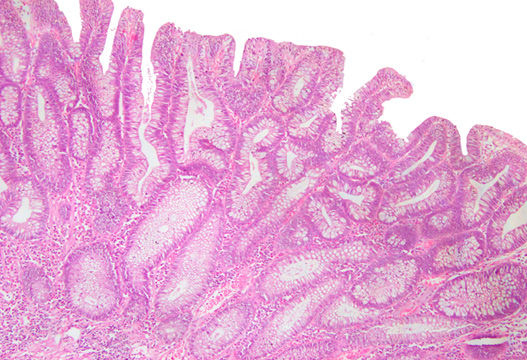

Photomicrograph

Figure 10: Photomicrograph of Adenomatous polyp Cyclin D1expression: Positive (Case No: 15, IHC X 40x).